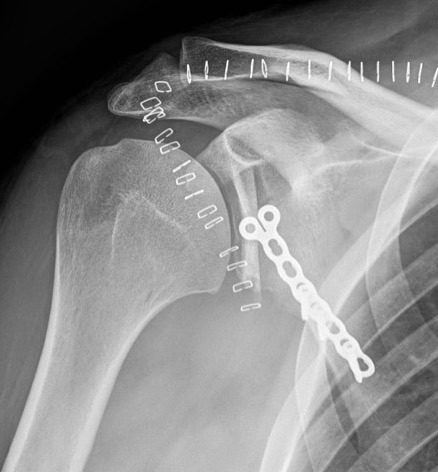

Beach chair or lateral

- posterior approach / detach deltoid / tentomy infraspinatus

- capsulotomy to expose glenoid

- osteotomy parallel to articular surface, 1.5 cm from articular surface

- preserves anterior 1 cm of glenoid to prevent iatrogenic fractures

- open 4 - 5 mm and insert bone graft

- +/- fixation